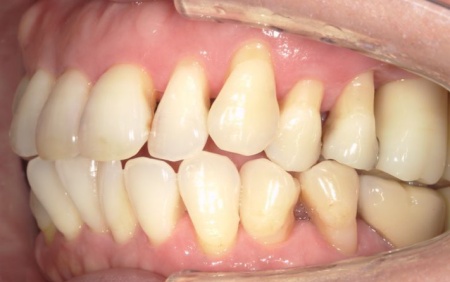

拝見したところ、左上の抜歯部周辺は歯を支える骨が溶ける「骨吸収」が進行し、隣接している歯を含めた複数の歯がひどくグラグラしており、温存が困難です。

噛み合わせも安定していなかったため、このままでは残っている歯への負担が増加し、歯の揺れやさらなる噛み合わせの悪化につながるリスクがあります。

骨吸収の影響で温存が難しい左上奥歯(第1大臼歯、第2大臼歯)と、大きく傾いてしまっている右下の親知らず(第3大臼歯)の3本は抜く必要があることをお伝えしました。

左上については、顎の骨が大きく失われているため、骨を再生させる処置「GBR(骨再生誘導法)」を実施してインプラントを支えるために必要な骨量を確保したうえで、インプラントを埋入する計画を立てました。

まずは左上奥歯2本を抜き、骨が足りない部分に骨補填剤を入れ骨の再生を促します。

経過観察後、十分な骨量を確保できたことを確認し、インプラントを埋入しました。